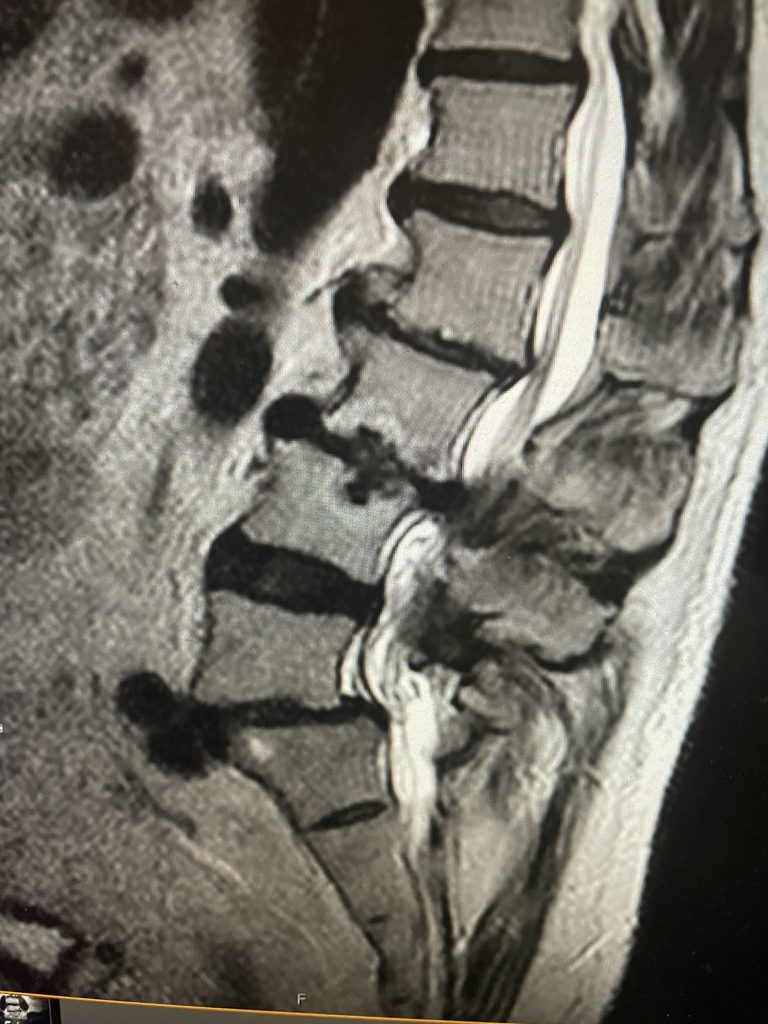

Figure 2. T2-weighted sagittal and axial MRIs demonstrating severe L3-4 stenosis and an L5-S1 grade 1 spondylolisthesis and spondylolysis and L3-4 retrolisthesis. Note the anterior osteophyte formation at L2-3 with attempted autostabilization of segment.

He had mild proximal weakness of his hip flexors. He also had a history of diabetes, hypertension, and hypercholesterolemia. Imaging studies were obtained. Plain x-rays (Fig. 1) demonstrated a degenerative levoscoliosis with the apex of the curve at L2-3. Lumbar MRI (Fig. 2) showed severe degenerative disc disease with an L5-S1 grade 1 spondylolisthesis and a significant retrolisthesis at L3-4 with severe lumbar stenosis.